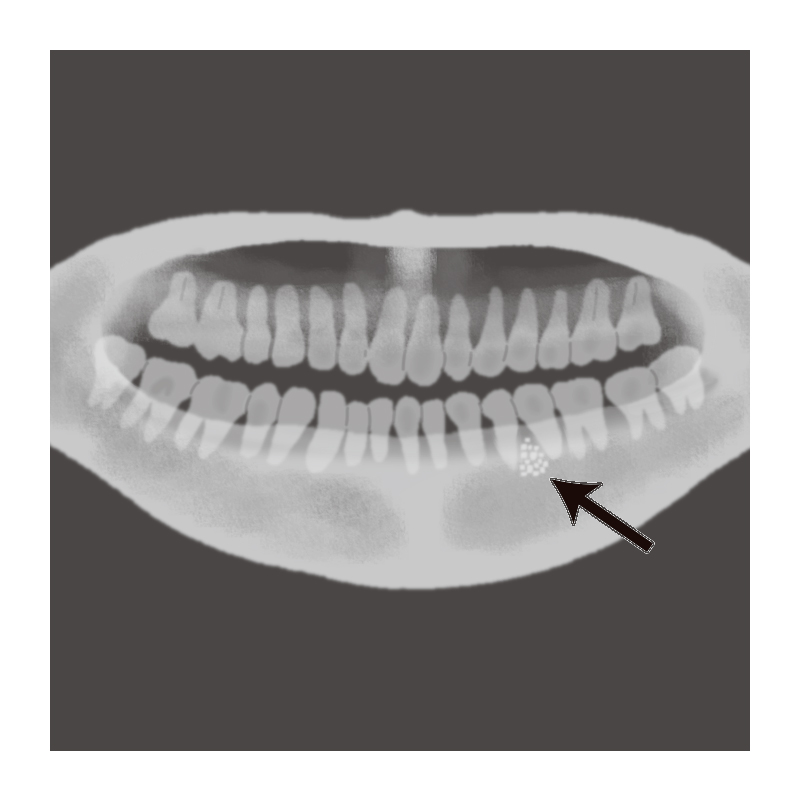

エナメル上皮腫の発生率が最も高く、ついで角化嚢胞性歯原性腫瘍、歯牙腫、骨関連腫瘍と続き、99%以上が良性腫瘍で、悪性腫瘍の発生はまれである。

- 歯牙腫

- 複雑型

- 集合型